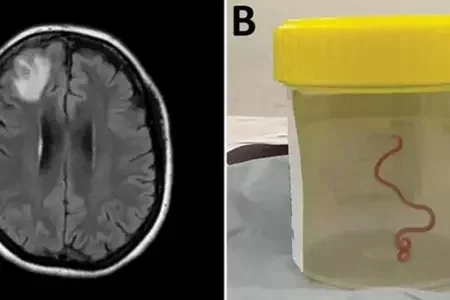

В Австралии женщина долгое время жаловалась на депрессию и проблемы с памятью. В ее мозгу нашли живого червя3